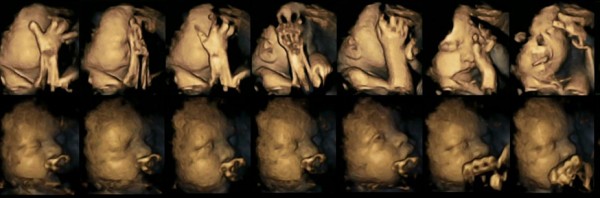

The images featured here show a foetus whose mother is a smoker (top) and a foetus whose mother is a non-smoker (bottom). We can see the foetus of the smoker looks distressed, its face almost twisted into a grimace, while the other foetus looks calmer and more serene.

When examining the 4D scans of pregnant non-smokers and pregnant smokers, they found that babies whose mothers smoked showed a much higher rate of mouth movements than those whose mothers didn’t.

As part of the study, 80 4D ultrasound scans were carried out on 20 foetuses, to assess mouth and touch movements. The scans were carried out at four different intervals between 24 and 36 weeks of pregnancy.